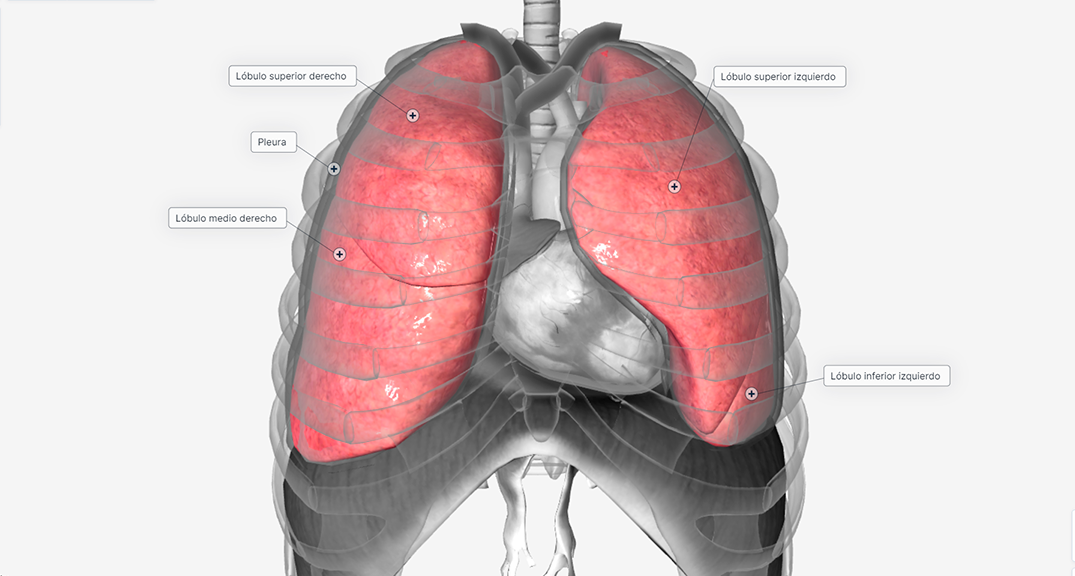

En el cáncer de pulmón en estadio I, los tumores son pequeños (miden menos de 5 cm) y se limitan a un pulmón. El tumor puede extenderse a través de la cubierta exterior de los pulmones (pleura).